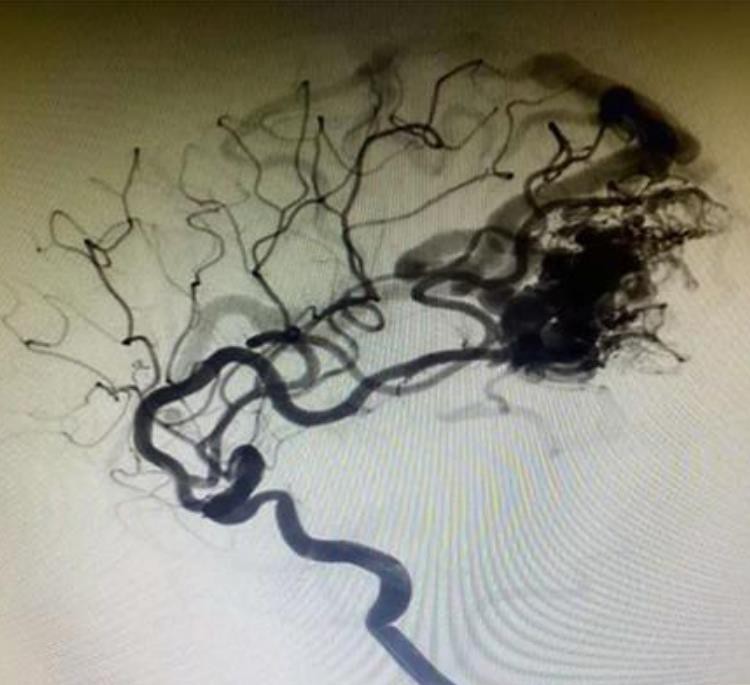

Tam ir labāka izkliede un iespiešanās. un tas var dziļi iekļūt bojājumā un sasniegt distālo trauku.

Tantalum pulveris ir smalkāks, lēnāk nogulsnējies un skaidrāk radiogrāfija, salīdzinot ar konkurentiem.